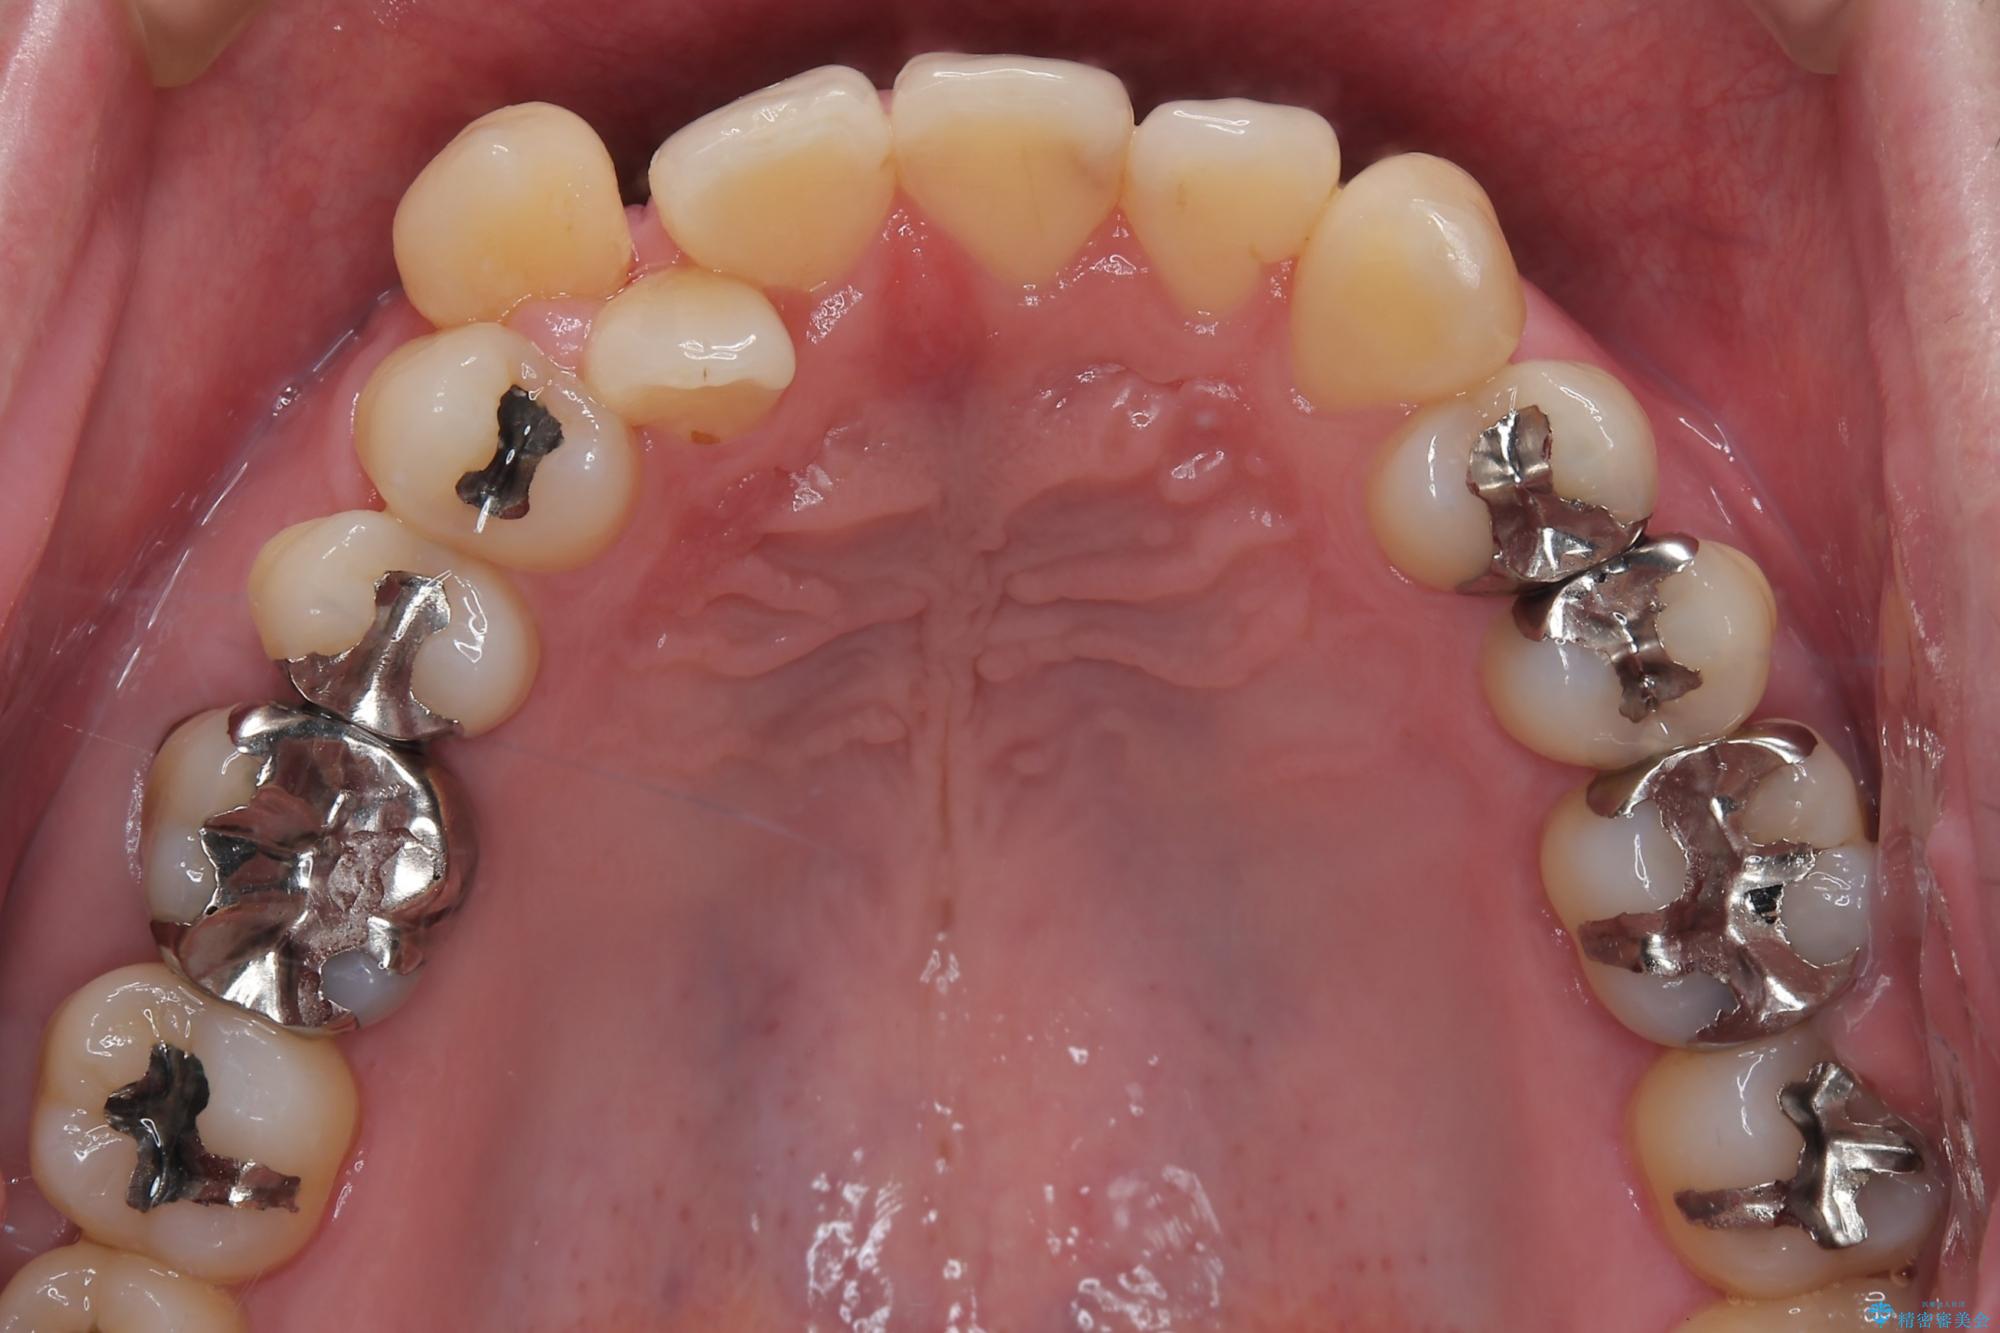

- 右上2番目の歯が舌側転位していることと前歯の叢生(がたつき)を主訴に来院されました。

右上の犬歯が初診時よりかなり歯根露出しており、矯正の力をかけるとさらに歯根露出するリスクがあるため、右上の2番目の歯を前に出すためにも

右上の犬歯を抜歯して歯並びを整える治療計画を立てました。

下のがたつきをとるために、IPR(歯と歯の間を削る処置)も行って歯を並べていきます。